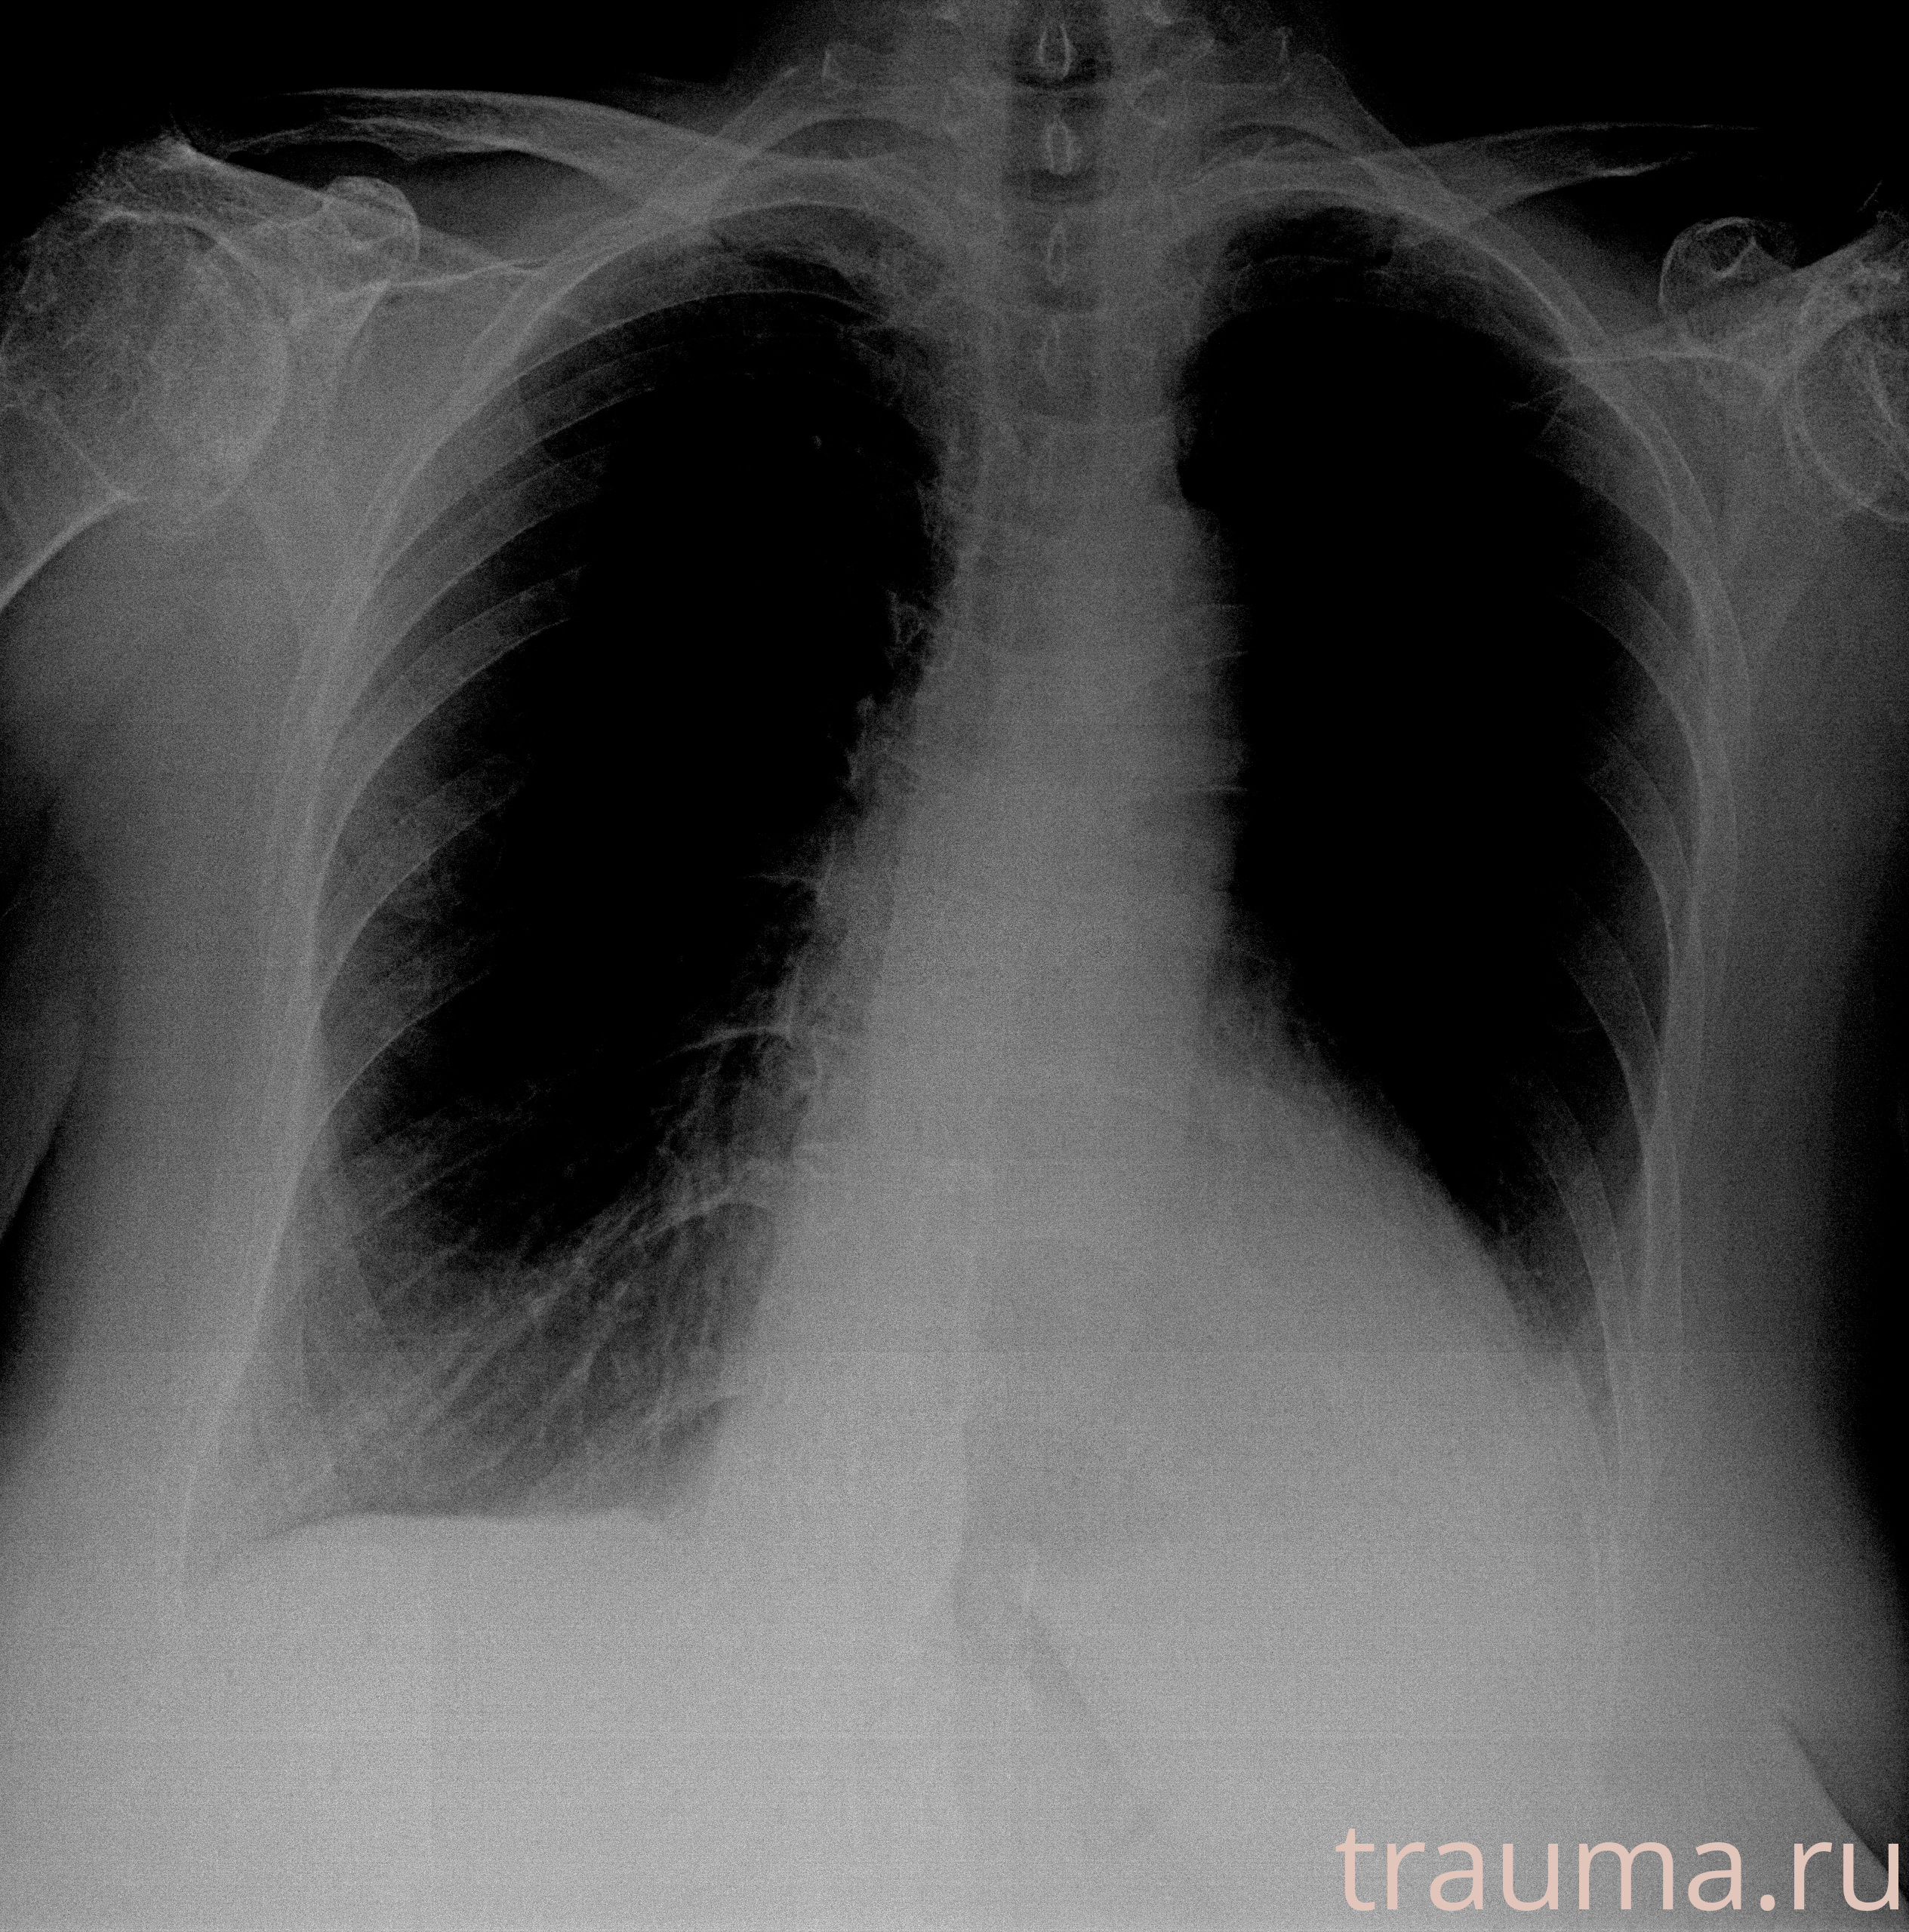

Рентген на дому: по вашему адресу приезжает врач-рентгенолог, травматолог-ортопед с мобильным рентгеновским аппаратом, проводит диагностику травмы или заболевания, делает необходимые рентгенограммы, дает рекомендации по дальнейшему лечению. Получить качественные снимки в домашних условиях возможно благодаря уникальной методике, разработанной МосРентген Центром для института  Склифосовского

при переломе шейки бедра и пневмонии от компании МосРентген Центр - партнера Института имени Склифосовского